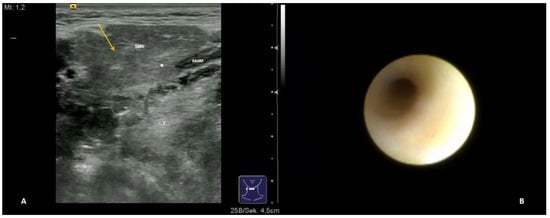

- Short duct stenosis (≤1 cm; Figure 3B; Supplementary Video S3)